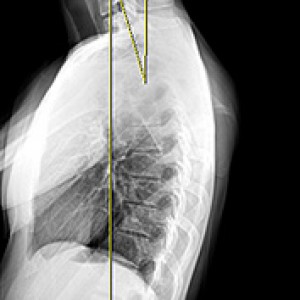

Before & After

해당 사진은 수정없는 실제 치료사진입니다.

환자의 치료결과는 환자의 상태, 치료방법 등에 따라 차이가 발생할 수 있습니다.